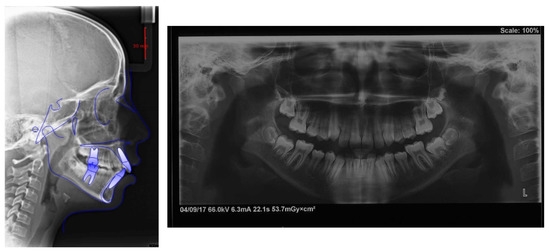

4. Case Report

4.1. Etiology and Diagnosis

4.2. Treatment Objectives

4.3. Treatment Strategy

4.4. Treatment Progress